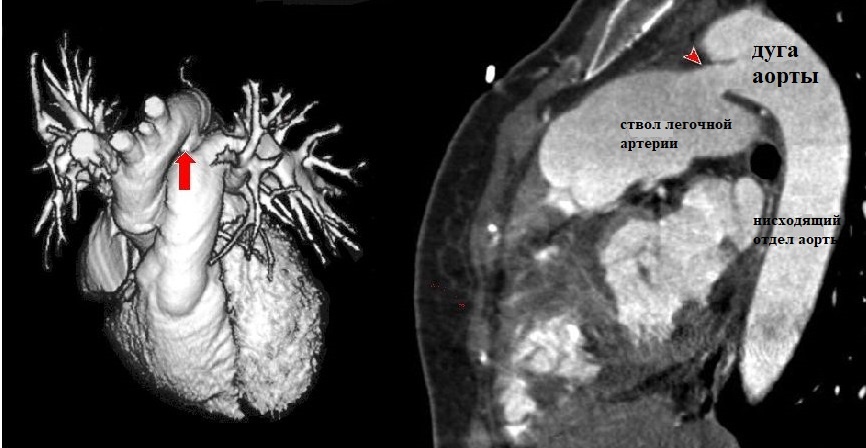

Объемная (слева) и сагиттальная (справа) реконструкции сердца и магистральных сосудистых стволов: стрелкой показан функционирующий шунт (возможности КТ-ангиографии)